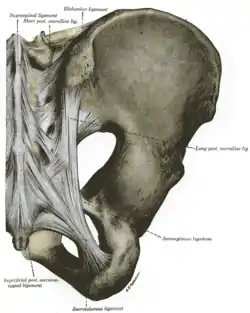

Ligaments

The ligaments of the sacroiliac joint include the following:[2]

- Anterior sacroiliac ligament

- Interosseous sacroiliac ligament

- Posterior sacroiliac ligament

- Sacrotuberous ligament

- Sacrospinous ligament

The posterior sacroiliac (SI) ligaments can be further divided into short (intrinsic) and long (extrinsic).[9] The dorsal interosseous ligaments are very strong ligaments. They are often stronger than bone, such that the pelvis may actually fracture before the ligament tears. The dorsal sacroiliac ligaments include both long and short ligaments. The long dorsal sacroiliac joint ligaments run in an oblique vertical direction while the short (interosseous) runs perpendicular from just behind the articular surfaces of the sacrum to the ilium and functions to keep the sacroiliac joint from distracting or opening. The sacrotuberous and sacrospinous ligaments (also known as the extrinsic sacroiliac joint ligaments) limit the amount the sacrum flexes.

The ligaments of the sacroiliac joint loosen during pregnancy due to the hormone relaxin; this loosening, along with that of the related symphysis pubis, permits the pelvic joints to widen during the birthing process. The long SI ligaments may be palpated in thin persons for pain and compared from one side of the body to the other; however, the reliability and the validity of comparing ligaments for pain have currently not been shown. The interosseous ligaments are very short and run perpendicular from the iliac surface to the sacrum, they keep the auricular surfaces from abducting or opening/distracting.